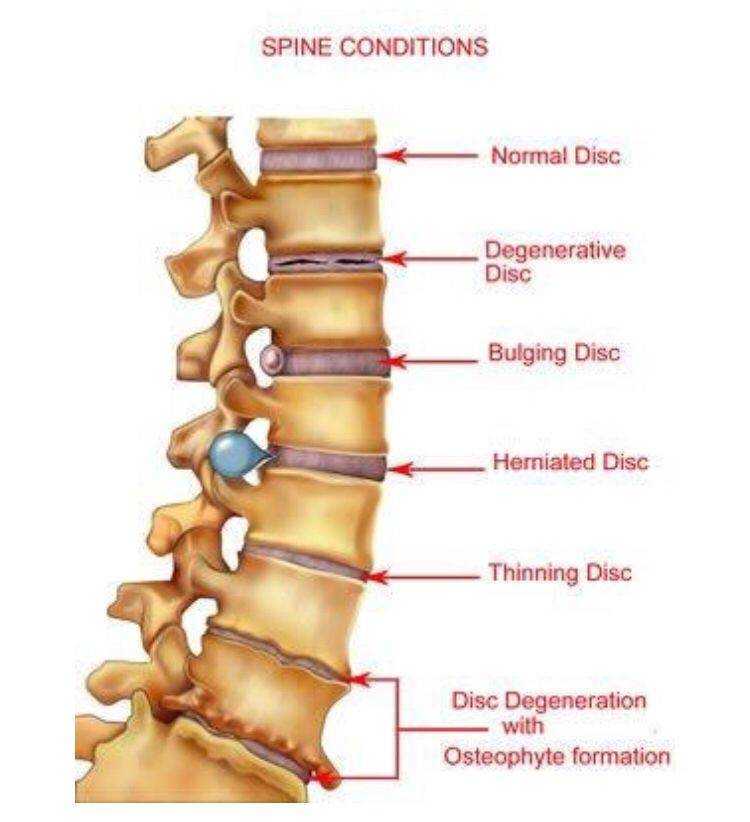

Мрт картина дегенеративно дистрофических изменений пояснично крестцового отдела позвоночника